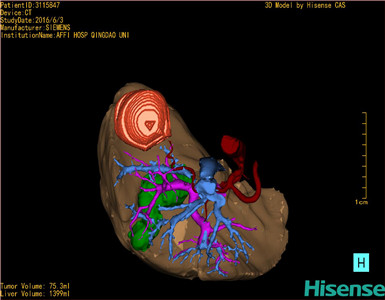

通过调节窗宽窗位调整CT序号,对肿瘤,肝实质,胆囊,下腔静脉,肿瘤,肝动脉、门静脉及肝静脉等进行三维重建;系统自动计算肿瘤体积和肝脏体积。

模拟手术操作,自动计算切除肿瘤体积。肝脏体积为1399ml,肿瘤体积为75.3ml,肿瘤体积为肝脏体积的5.4%,通过比对70-80岁正常肝脏体积为1118.08±190.14 ml,通过术前模拟手术,精准判断切除后剩余肝脏体积能耐受,避免肝衰竭发生。

术前三维重建:重建图片